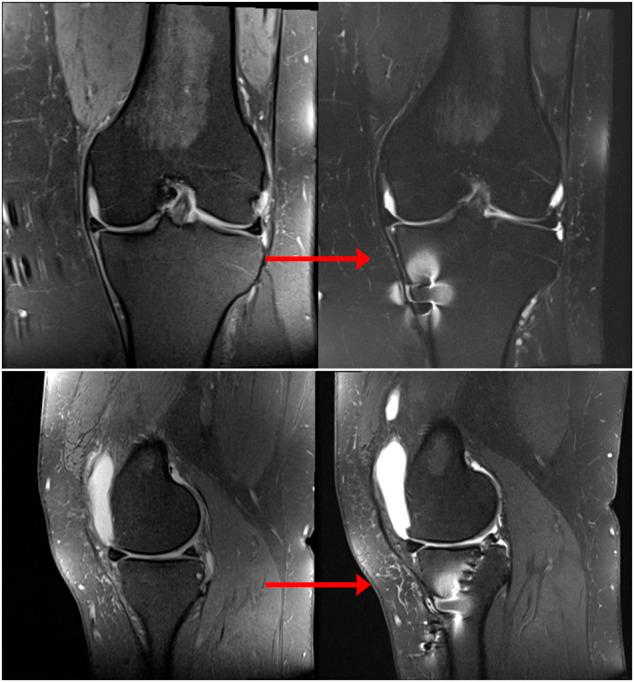

Posterior medial meniscus root tears (PMMRTs) make up a relatively notable proportion of all meniscus pathology and have been definitively linked to the progression of osteoarthritis (OA). While known risk factors for development of OA in the knee include abnormal tibial coronal alignment, obesity and female gender, PMMRTs have emerged in recent years as another significant driver of degenerative disease. These injuries lead to an increase in average contact pressure in the medial compartment, along with increases in peak contact pressure and a decrease in contact area relative to the intact state. Loss of the root attachment impairs the function of the entire meniscus and leads to meniscal extrusion, thus impairing the force-dissipating role of the meniscus. Anatomic meniscus root repairs with a transtibial pullout technique have been shown biomechanically to restore mean and peak contact pressures in the medial compartment. However, nonanatomic root repairs have been reported to be ineffective at restoring joint pressures back to normal. Meniscal extrusion is often a consequence of nonanatomic repair and is correlated with progression of OA. In this study, the authors will describe the biomechanical basis of the natural history of medial meniscal root tears and will support the biomechanical studies with a case series including patients that either underwent non-operative treatment (5 patients) or non-anatomic repair of their medial meniscal root tears (6 patients). Using measurements derived from axial MRI, the authors will detail the distance from native root attachment center of the non-anatomic tunnels and discuss the ongoing symptoms of those patients. Imaging and OA progression among patients who were treated nonoperatively before presentation to the authors will be discussed as well. The case series thus presented will illustrate the natural history of meniscal root tears, the consequences of non-anatomic repair, and the findings of symptomatic meniscal extrusion associated with a non-anatomic repair position of the meniscus.

后内侧半月板根部撕裂(PMMRTs)在所有半月板病变中占比较显著,并且已明确与骨关节炎(OA)的进展相关。虽然已知膝关节OA发展的风险因素包括胫骨冠状面排列异常、肥胖和女性性别,但近年来PMMRTs已成为退行性疾病的另一个重要驱动因素。这些损伤导致内侧间室平均接触压力增加,同时峰值接触压力增加,且相对于完整状态接触面积减小。根部附着的丧失会损害整个半月板的功能,并导致半月板挤出,从而损害半月板的力消散作用。经胫骨拉出技术进行的解剖学半月板根部修复在生物力学上已显示可恢复内侧间室的平均和峰值接触压力。然而,据报道非解剖学根部修复在将关节压力恢复到正常水平方面无效。半月板挤出通常是非解剖学修复的结果,并且与OA的进展相关。在本研究中,作者将描述内侧半月板根部撕裂自然病程的生物力学基础,并将通过一个病例系列来支持生物力学研究,该病例系列包括接受非手术治疗的患者(5例)或内侧半月板根部撕裂接受非解剖学修复的患者(6例)。作者将使用从轴向MRI得出的测量值,详细说明非解剖学隧道与天然根部附着中心的距离,并讨论这些患者的持续症状。还将讨论在向作者就诊之前接受非手术治疗的患者的影像学和OA进展情况。因此呈现的病例系列将说明半月板根部撕裂的自然病程、非解剖学修复的后果以及与半月板非解剖学修复位置相关的有症状半月板挤出的发现。